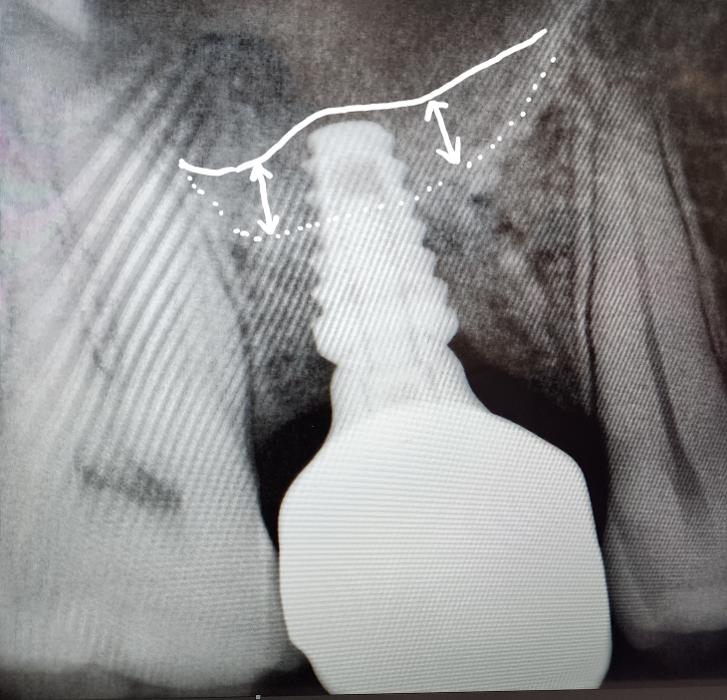

Bone Grafting

Bone grafting is an essential procedure often performed in conjunction with dental implant planning. When the natural bone volume is insufficient, bone grafting is incorporated to address the deficiency. At ICS Dental Studio, Dr Skaf utilises bone grafting techniques to rebuild and augment the jawbone, providing a solid foundation for successful dental implant placement. This procedure is planned carefully to ensure optimal results and long-term implant stability. Bone grafting is necessary when there is insufficient bone volume, preserving the jawbone and enhancing the overall success of dental implant treatments.

A bone graft repairs bones damaged from trauma or depleted due to conditions such as periodontal disease.